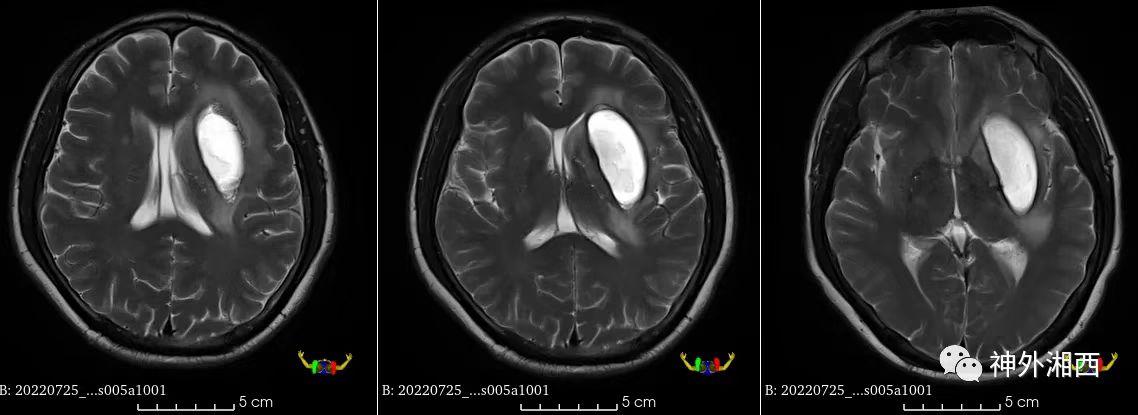

术前MRI示血肿稳定,且液化良好